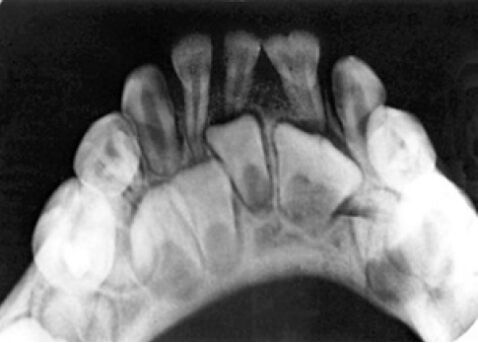

68.附圖X光片中,左下門齒有何形態異常? (A)雙生齒(gemination) (B)融合齒(fusion of teeth) (C)連合齒(concrescence) (D)巨齒症(macrodontia)